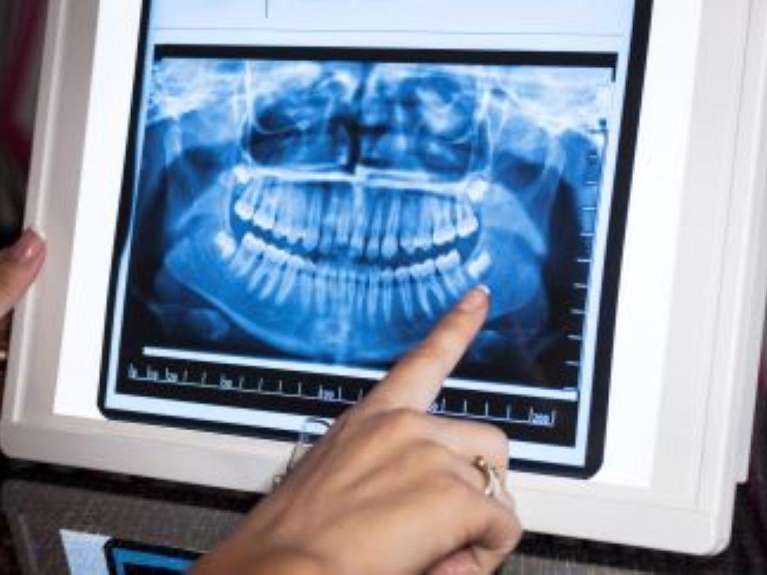

Panoramic X-Rays

A panoramic x-ray can show us all your teeth simultaneously because it moves completely around your head. When we plan dental surgeries or implant placement, panoramic x-rays can show us your teeth, jaw joints, bone levels and sinuses.